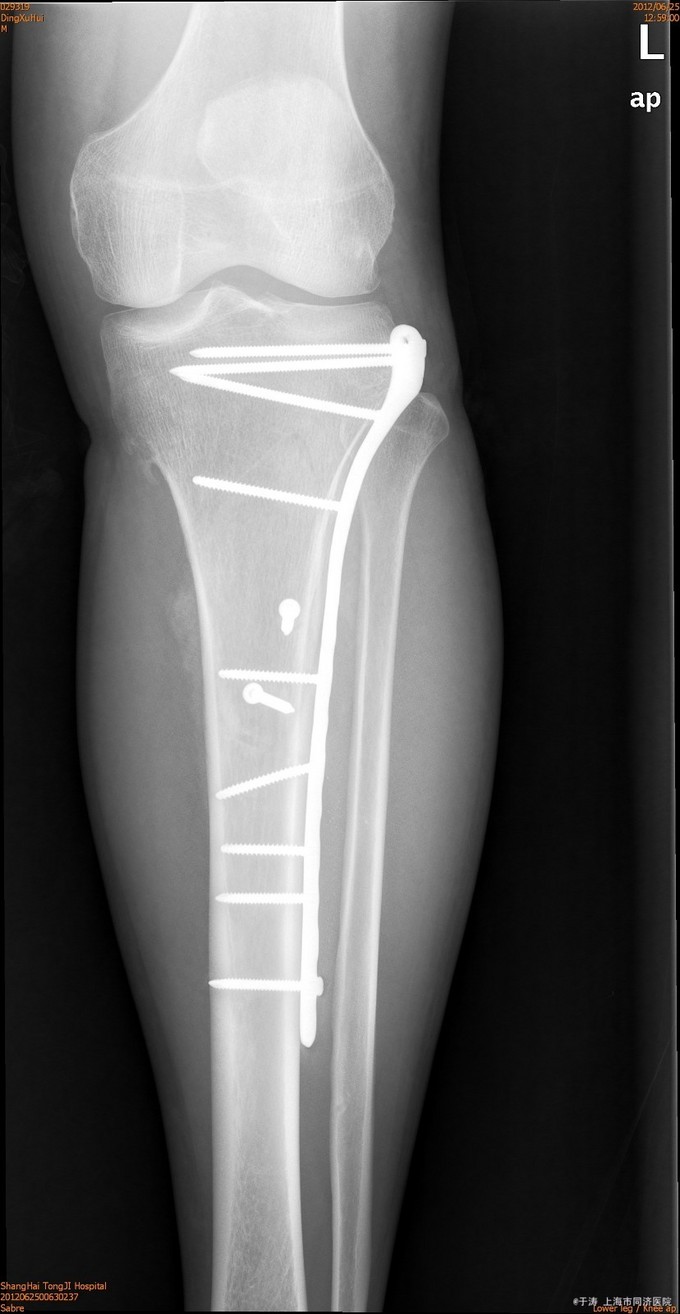

患者男,38岁,车祸后左膝肿痛9小时入院。患者9小时前车祸撞伤,于我院急诊就诊,X线及CT示:盆腔积液、左肾囊肿、蛛网膜下腔出血、左胫骨近端骨折。遂收治入院。

诊断为左胫骨近端骨折,兄弟科室对症处理、生命体征平稳后,行左胫骨近端骨折ORIF术,术后抗炎、补液对症处理。

术后4月随访,复位可,骨折愈合可,力线可,内固定在位。对于胫骨近端骨折,ORIF术效果确凿。